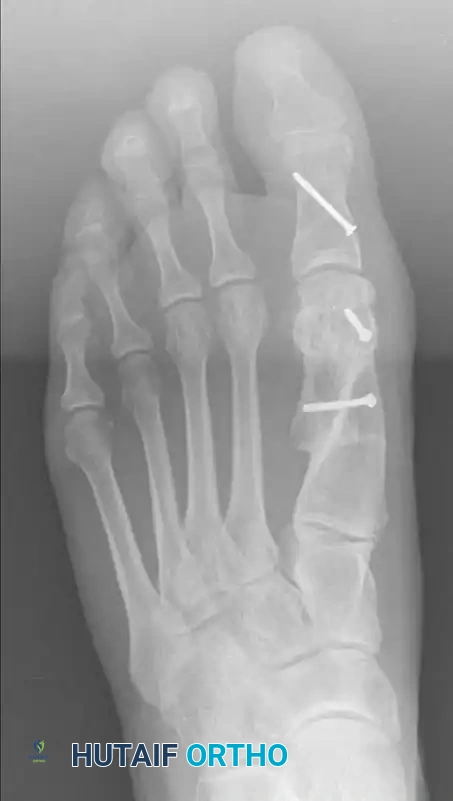

التثبيت النهائي باستخدام المسامير

بمجرد التأكد من الوضع المثالي للعظام، يتم التثبيت النهائي باستخدام مسمارين معدنيين صغيرين جدا من التيتانيوم. توفر هذه المسامير استقرارا قويا يسمح للمريض ببدء تحميل الوزن على القدم في وقت مبكر. بعد ذلك، يتم إزالة أي بروز عظمي متبقي لضمان مظهر طبيعي ومسطح للقدم.

تصل نسبة رضا المرضى عن نتائج عملية سكارف إلى حوالي تسعين بالمائة. يلاحظ المرضى اختفاء الألم المزعج، وتحسن مظهر القدم بشكل ملحوظ، وقدرتهم على ارتداء الأحذية العادية براحة تامة. ومع ذلك، يجب أن يدرك المريض أن التورم الخفيف قد يستمر لعدة أشهر بعد الجراحة، وهو أمر طبيعي تماما.

مقارنة قبل وبعد الجراحة

للحفاظ على النتائج الممتازة للجراحة على المدى الطويل، ينصح الأطباء بتجنب العودة لارتداء الأحذية الضيقة جدا أو ذات الكعب العالي المبالغ فيه لفترات طويلة. العناية بصحة القدم واختيار الأحذية الداعمة والمريحة يضمن عدم عودة التشوه ويحافظ على صحة المفاصل.